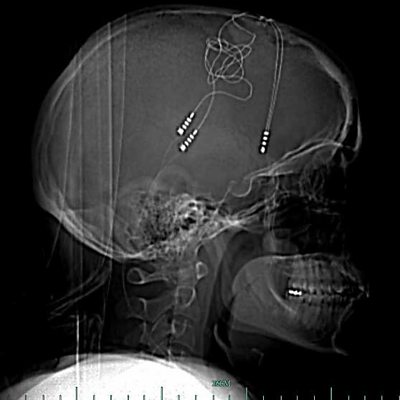

When all the other treatments failed to help her depression Brandy Ellis turned to technology. She now has electronics in her brain to regulate her emotions. She explains whether she feels more or less human as a result.